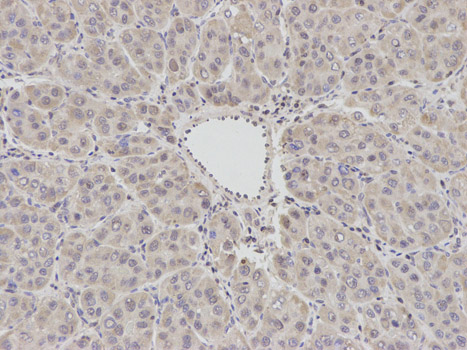

BCL2, Polyclonal Antibody (Cat# AAA28239)

BCL2, Polyclonal Antibody (Cat# AAA29670)